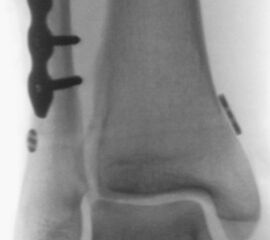

Liegt eine Syndesmosen-Insuffizienz vor (Abbildung 18), so erfolgt nach der Osteosynthese aller Frakturen im ersten Schritt die Reposition der Fibula in die Incisura fibularis der Tibia mittels Repositionszange. Danach sollte geprüft werden, ob die Dorsalextension im OSG noch uneingeschränkt möglich ist. Falls vorhanden, ist es hilfreich die korrekte Reposition mittels intraoperativen CT zu kontrollieren. Die Durchführung eines intraoperativen 3D Scans konnte nach zufriedenstellenden Ergebnissen in der konventionellen 2D Bildgebung bereits intraoperativ in 20-40% ein korrekturbedürftiges Ergebnis zeigen 3132. Anschließend erfolgt das Einbringen einer Stellschraube oder eines Tight Ropes (Abbildung 19). Dabei sollte darauf geachtet werden, dass die Bohrung knapp proximal des distalen Tibio-Fibular-Gelenkes angelegt wird. Die Bohrung sollte in 30° von posterior nach anterior und parallel zur Gelenklinie des OSG gerichtet sein. Beim Einbringen der Schraube ist darauf zu achten, die Fibula nicht an die Tibia zu komprimieren. Postoperativ empfehlen wir die Durchführung einer CT-Untersuchung des verletzten und des unverletzten Sprunggelenkes. Nur so ist aus unserer Sicht die Reposition der Fibula sicher zu beurteilen.